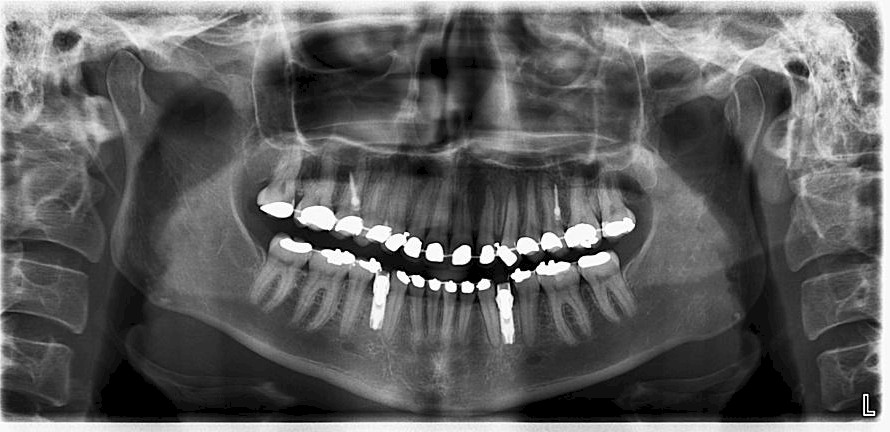

Un travail collaboratif

L’orthodontiste doit travailler en collaboration avec une équipe d’autres spécialistes pour définir un calendrier thérapeutique et donner au patient adulte le meilleur résultat.

- Intégrer la réalisation des prothèses et des implants

- Diagnostiquer les différents stades de la maladie parodontale (maladie de l’os et des gencives) et des facteurs de risque associés.

- Déterminer les cas nécessitant une intervention chirurgicale orthognathique.